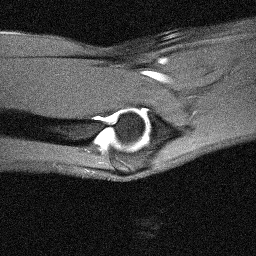

Orientation-specific examples grouped by anatomy. Select a category to view axial, coronal, and sagittal samples.

Coronal

Coronal sample